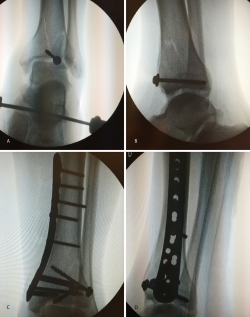

Nos colocamos sentados frente al miembro lesionado, elevando la mesa quirúrgica con la pantalla de la torre de artroscopia frente a nosotros. Tras realizar los portales de artroscopia, procedemos a un lavado exhaustivo de la articulación dejando introducir el suero de la bolsa de artroscopia (no utilizamos bomba de presión) hasta que dejen de salir restos de hematoma por el aspirador de artroscopia. A continuación, introducimos el sinoviotomo y resecamos el hemartros fracturario hasta que identifiquemos los fragmentos del foco de fractura (Figuras 4 y 5).

Posteriormente, realizamos un orificio en la cortical de la diáfisis de la tibia a cierta distancia del foco de fractura mediante una broca canulada de 8 mm que nos permita introducir un impactor curvo con el que percutir en el fragmento hundido hasta colocarlo a nivel de la superficie articular, controlando la reducción por artroscopia y radioscopia de manera simultánea.

Una vez reducida la fractura, fijamos los fragmentos de manera provisional con una o más agujas de Kirschner y las vamos sustituyendo por tornillos canulados de 4,5 mm. Cuando realizamos este procedimiento, ampliamos habitualmente un centímetro la herida de introducción del tornillo para poder colocar un pequeño separador que nos permita rechazar los elementos neurovasculares y tendinosos de la zona del tobillo.

En cuanto al postoperatorio, inmovilizamos al paciente con una férula de yeso hasta las 3 semanas. A partir de ese momento, colocamos una férula de material termoplástico que se puede retirar para movilizar el tobillo, iniciando la carga con una bota ortésica de tipo Walker a las 6-8 semanas (Figuras 6 a 11).

Figura 8. Percusión del fragmento con el impactor, control radioscópico de la posición del impactor e imagen artroscópica del escalón articular antes de la reducción.